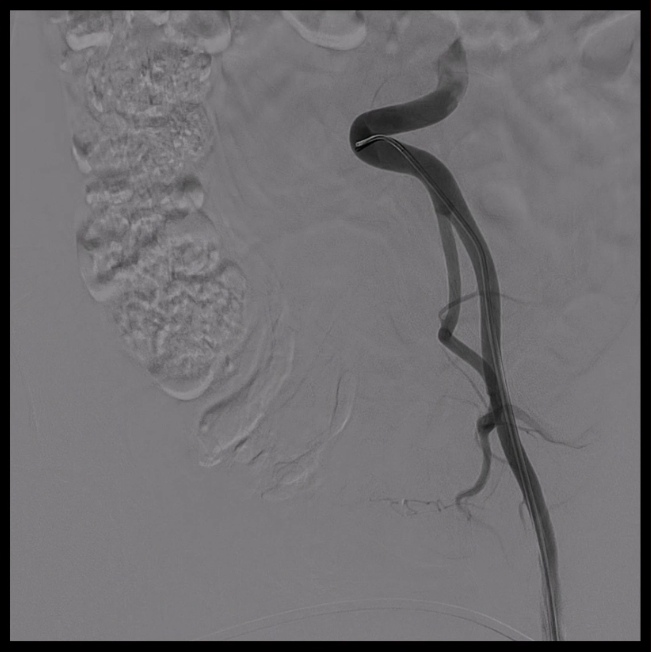

5. 支架释放与球囊预扩

释放支架主体,之后,头端后释放打开后将支架输送系统缓慢撤出。

分别经分支导丝送入球囊扩张支架分支覆膜部分,确保贴附良好。

6. 裸支架置入,球囊后扩张

于无名动脉、左颈总动脉及左锁骨下动脉开口位置处释放裸支架,维持血流通畅。

球囊后扩,优化支架形态及贴壁性,减少内漏风险。

术后造影显示,主动脉支架定位精准,三分支支架内血流通畅,夹层内仅有少量膜渗情况。从手术即刻效果来看,该治疗方案达到了预期目标,有效修复了主动脉夹层,恢复了血管的正常解剖结构和血流动力学状态。